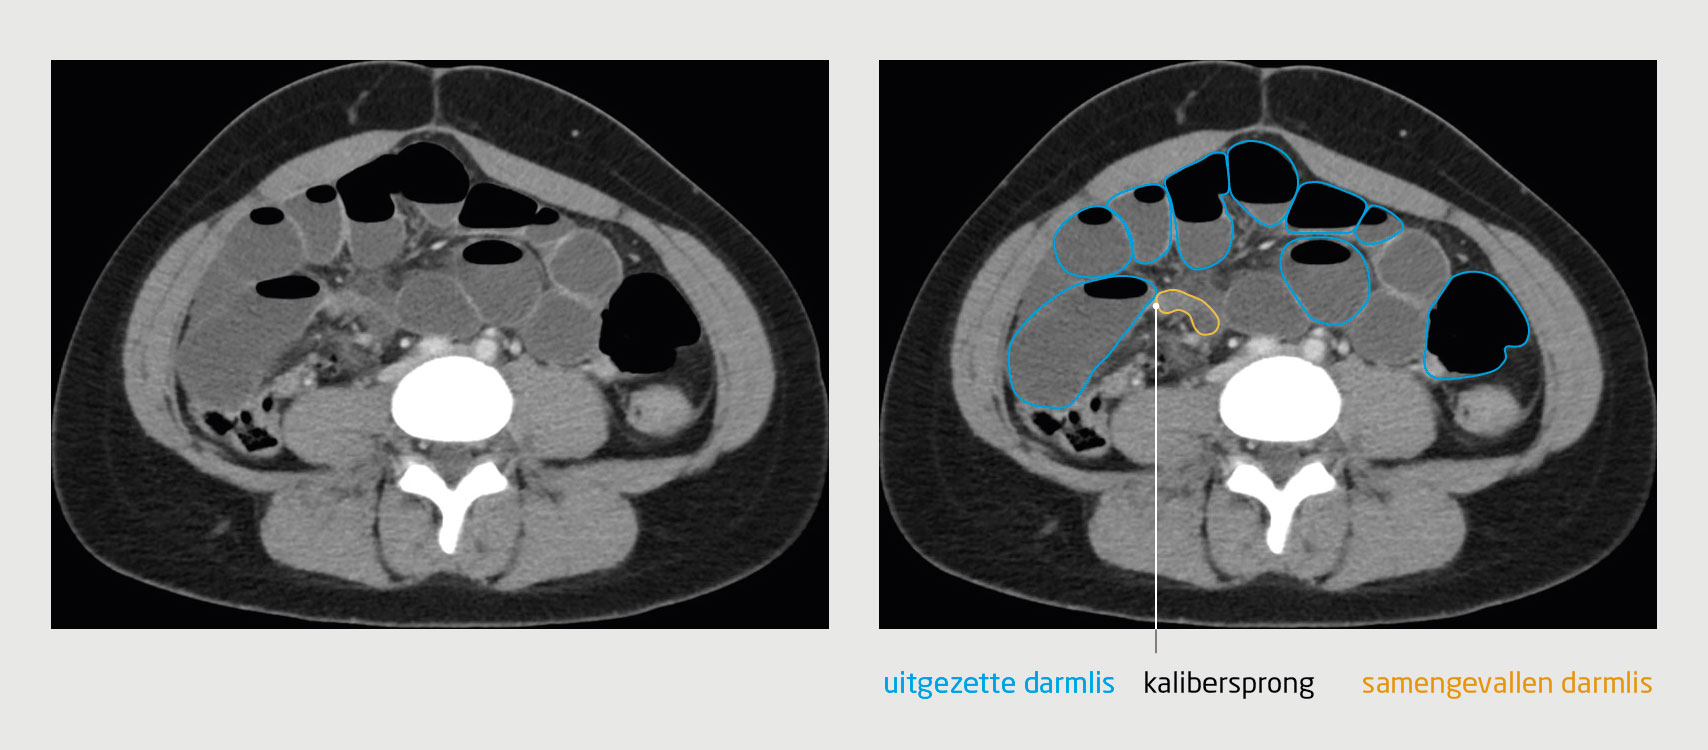

Om adhesies in beeld te brengen moet daarom worden gekeken naar secundaire kenmerken. Tijdens een episode van strengileus kunnen de uitgezette darmlissen proximaal van de obstructie goed in beeld worden gebracht (figuur 3). De aanwezigheid van een dergelijke kalibersprong zonder andere afwijkingen is zeer kenmerkend voor een strengileus. Dit kenmerk is echter niet bruikbaar bij chronische pijn.

Figuur 3

CT-beeld bij een strengileus

Figuur 3 | CT-beeld bij een strengileus

CT-scan van het abdomen bij een patiënt met een strengileus. De positie van de streng is af te leiden uit de kalibersprong tussen de uitgezette darmlis en de normale darmlis, die samengevallen is.